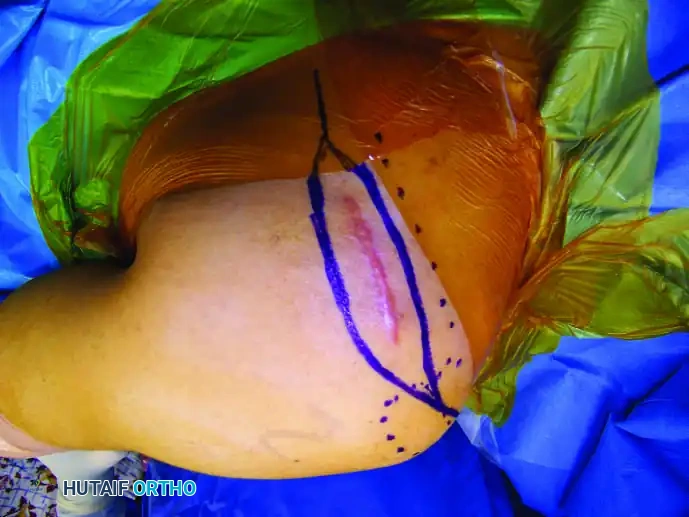

1. The locking mechanism is located via palpation or fluoroscopy.

2. The patient’s limb is marked at the exact site of the internal mechanism.

3. An electromagnetic coil is placed circumferentially around the limb at the marked level.